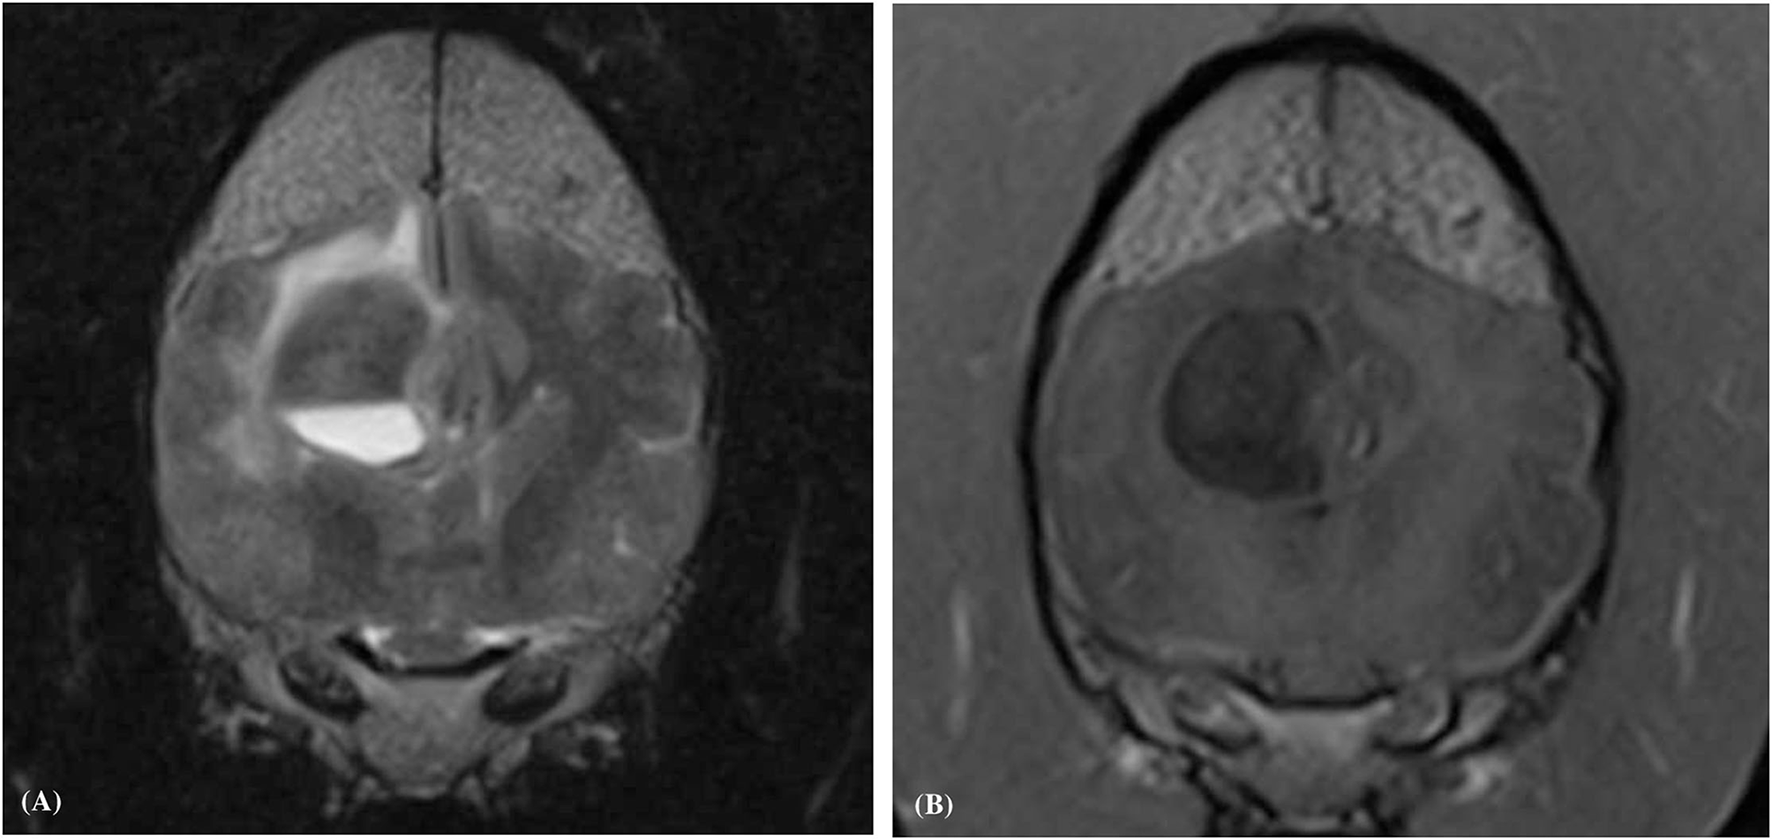

Figure 4

Transverse plane T1-weighted (A), and T1-weighted post contrast (B), images of a dog (Case 4) with an intracranial intra-axial hematoma affecting the white matter of the left fronto-parietal lobe. The lesion displays an obvious peripheral contrast enhancement pattern (long white arrows) (B). Transverse plane T1-weighted (C), and T1-weighted post contrast (D) images of dog (Case 1) with a hematoma lesion affecting the white matter of the medial aspect of the left temporo-frontal lobe and internal capsule. The lesion displays a faint and focal area of peripheral contrast enhancement (short white arrow). Neither lesions post contrast (B,D) show enhancement of their central regions.

Contrast enhancement was evident in (6/10) hematomas and absent in (4/10) cases. When present the enhancement was always present at the periphery of the hematoma (Figures 2, 4). Enhancement was deemed obvious in (4/6) and faint in (2/6) cases. There were no regions of central enhancement within any of the hematoma lesions. Perilesional oedema was classified as moderate in (6/10) and mild in (4/6) hematomas. A mass effect was associated with all hematoma lesions. The mass effect was deemed moderate in (6/10), mild (3/10) and marked in (1/10) of the hematoma cases. A lateral shift of the falx cerebri was noted in (7/10) cases, compression of the lateral ventricles in (4/10) cases, and caudal transtentorial herniation was observed in a single case.